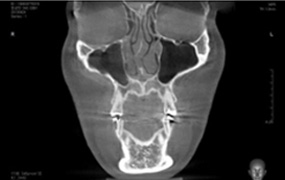

3D-CT

입체분석

을 통한

심층검사

수술 전 3D-CT 입체 분석을 통해

환자의 코 뼈는 물론 코 주변 연부 조직의

모양, 상태, 크기까지 정밀하게 검사하여

환자 개개인에 맞는 1:1 맞춤 수술을 계획합니다.

연골 비대칭 및

비중격 만곡증의 유무

하비갑개 비후 및

코막힘 문제해결

비중격 연골의

상태와 크기 분석

코 뼈의 넓이